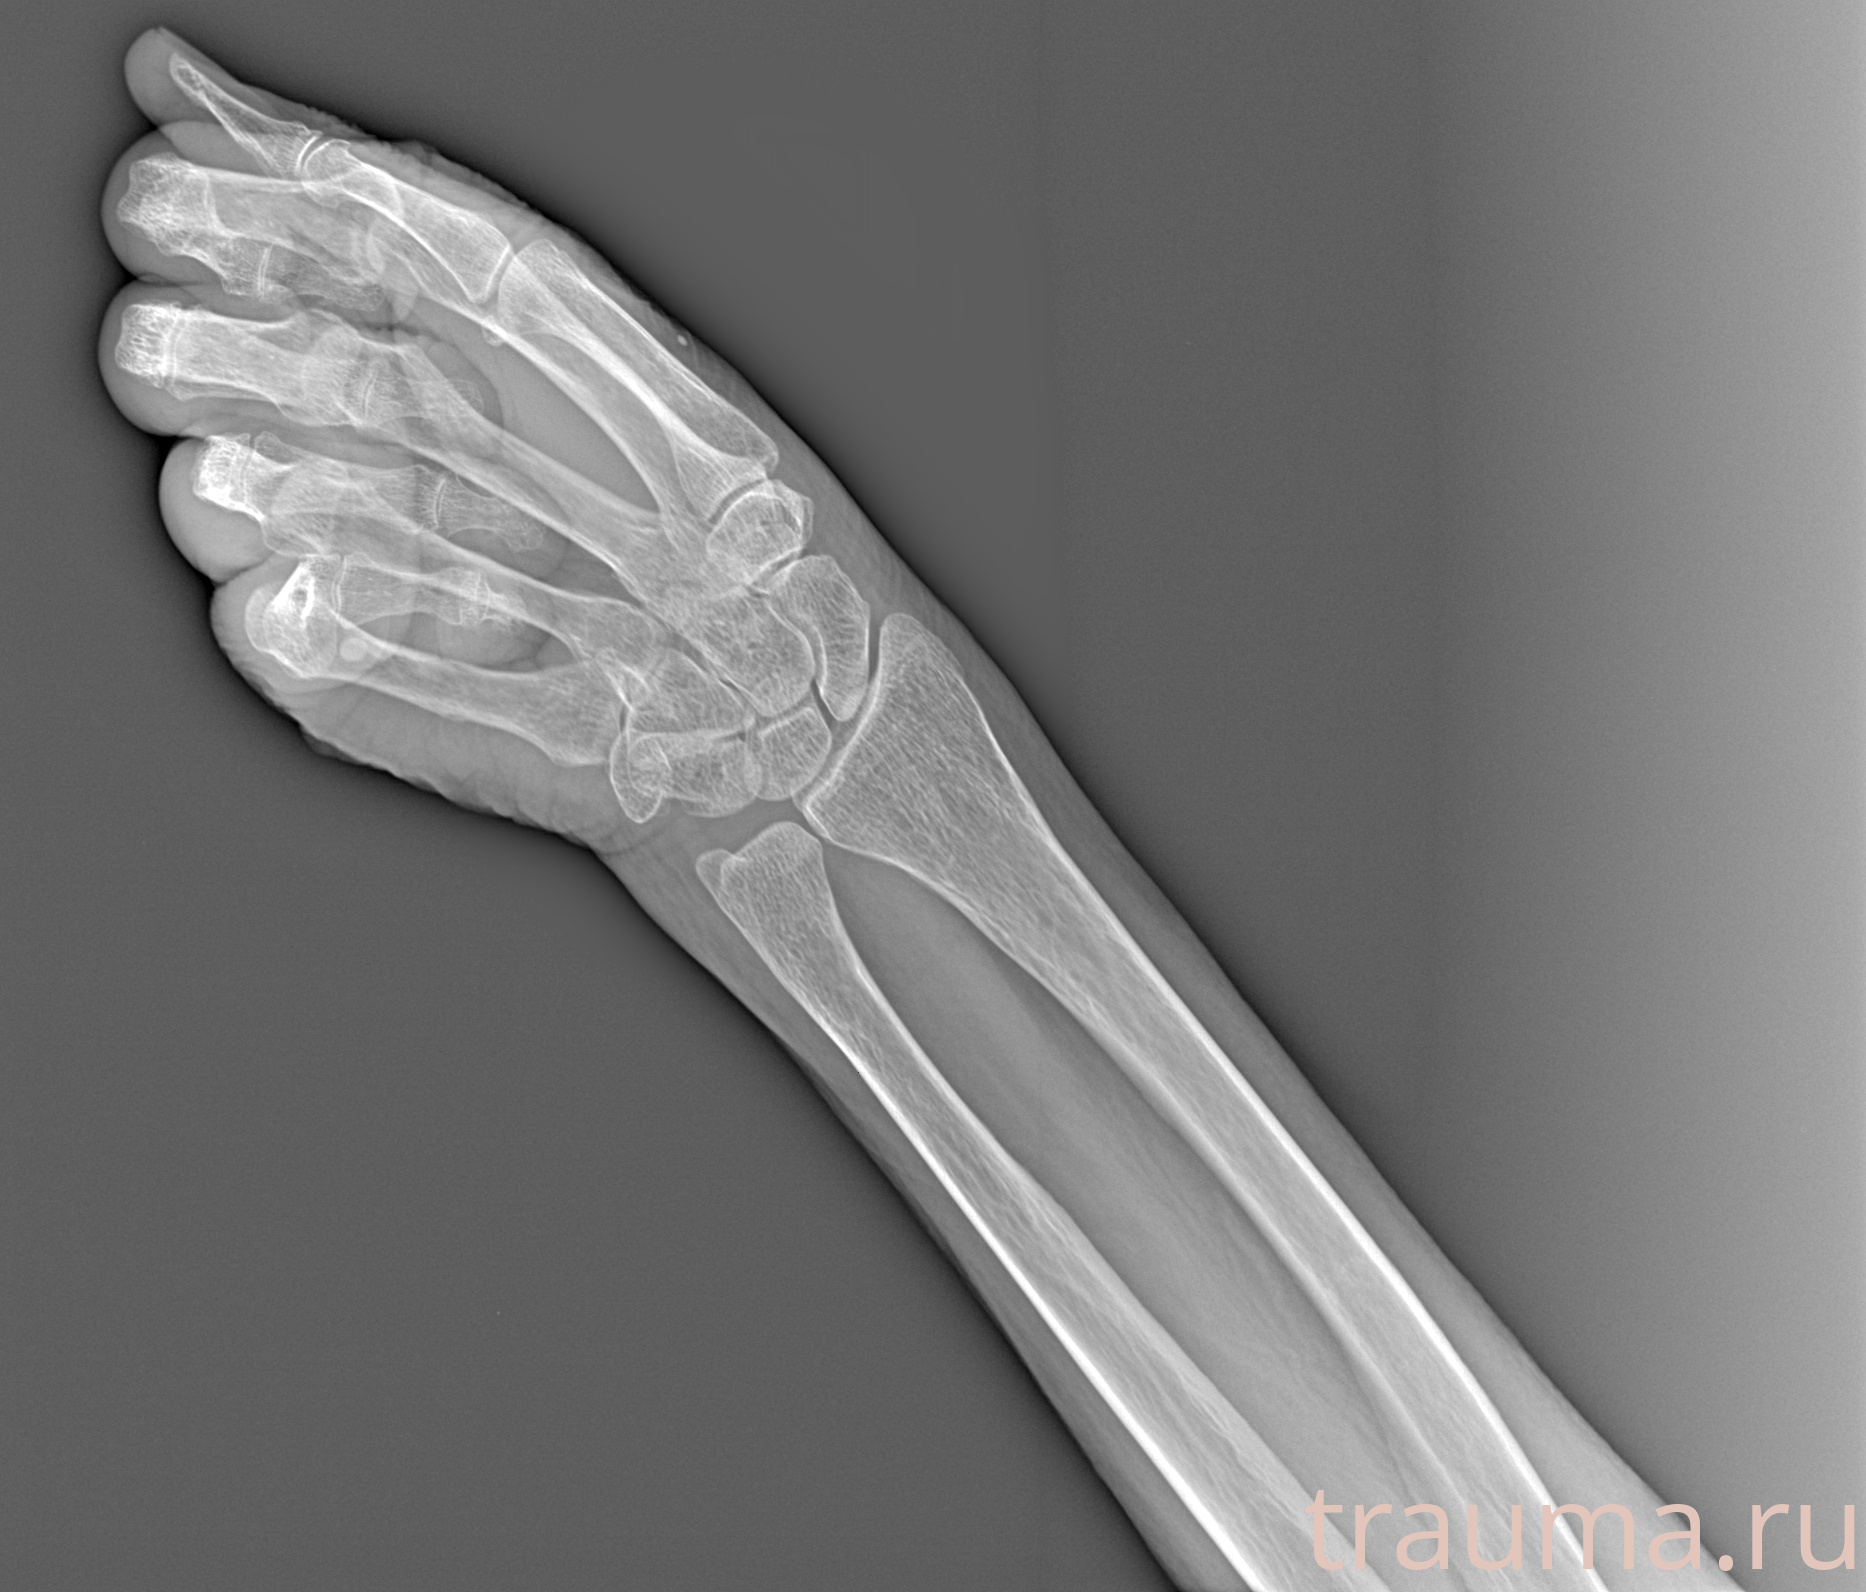

Рентген на дому: по вашему адресу приезжает врач-рентгенолог, травматолог-ортопед с мобильным рентгеновским аппаратом, проводит диагностику травмы или заболевания, делает необходимые рентгенограммы, дает рекомендации по дальнейшему лечению. Получить качественные снимки в домашних условиях возможно благодаря уникальной методике, разработанной МосРентген Центром для института  Склифосовского